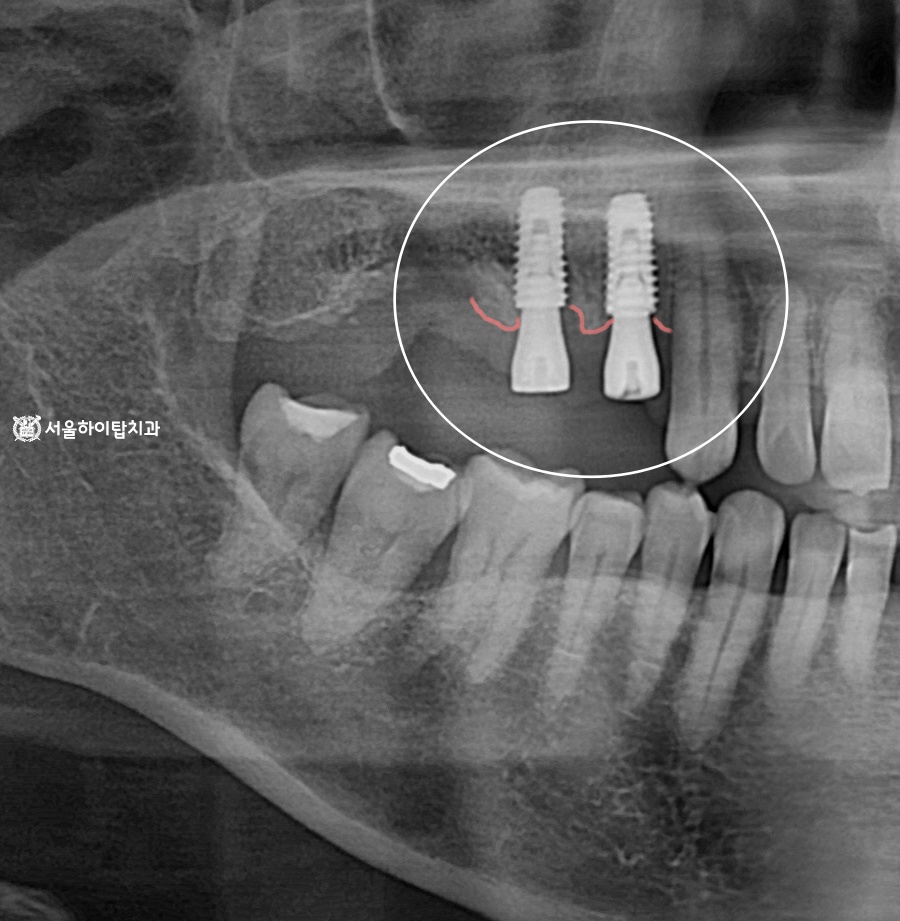

임플란트 당일 식립 과정

앞서 계획과 CT 데이터를 바탕으로, 발치 후 임플란트가 당일 즉시 식립된 모습입니다.

오른쪽 사진은 초진 사진인데,

주안역 치과 에서 임의로 표시한 선을 보면

W자 형태의 뼈가 형성되어 있는 것을 확인할 수 있습니다.

이 구조를 septum bone, 즉 치근 사이에 남아 있는 뼈의 칸막이라고 부릅니다.

쉽게 말하면, 치아가 여러 뿌리를 가진 어금니 사이에 남아 있는 작은 뼈라고 생각하면 됩니다.

이 W자 뼈가 있으면, 임플란트를 심을 때

남아 있는 뼈를 지지 구조로 활용할 수 있어 안정적입니다.

따라서 #16 제외하고 당일 식립이 가능했던 것입니다.